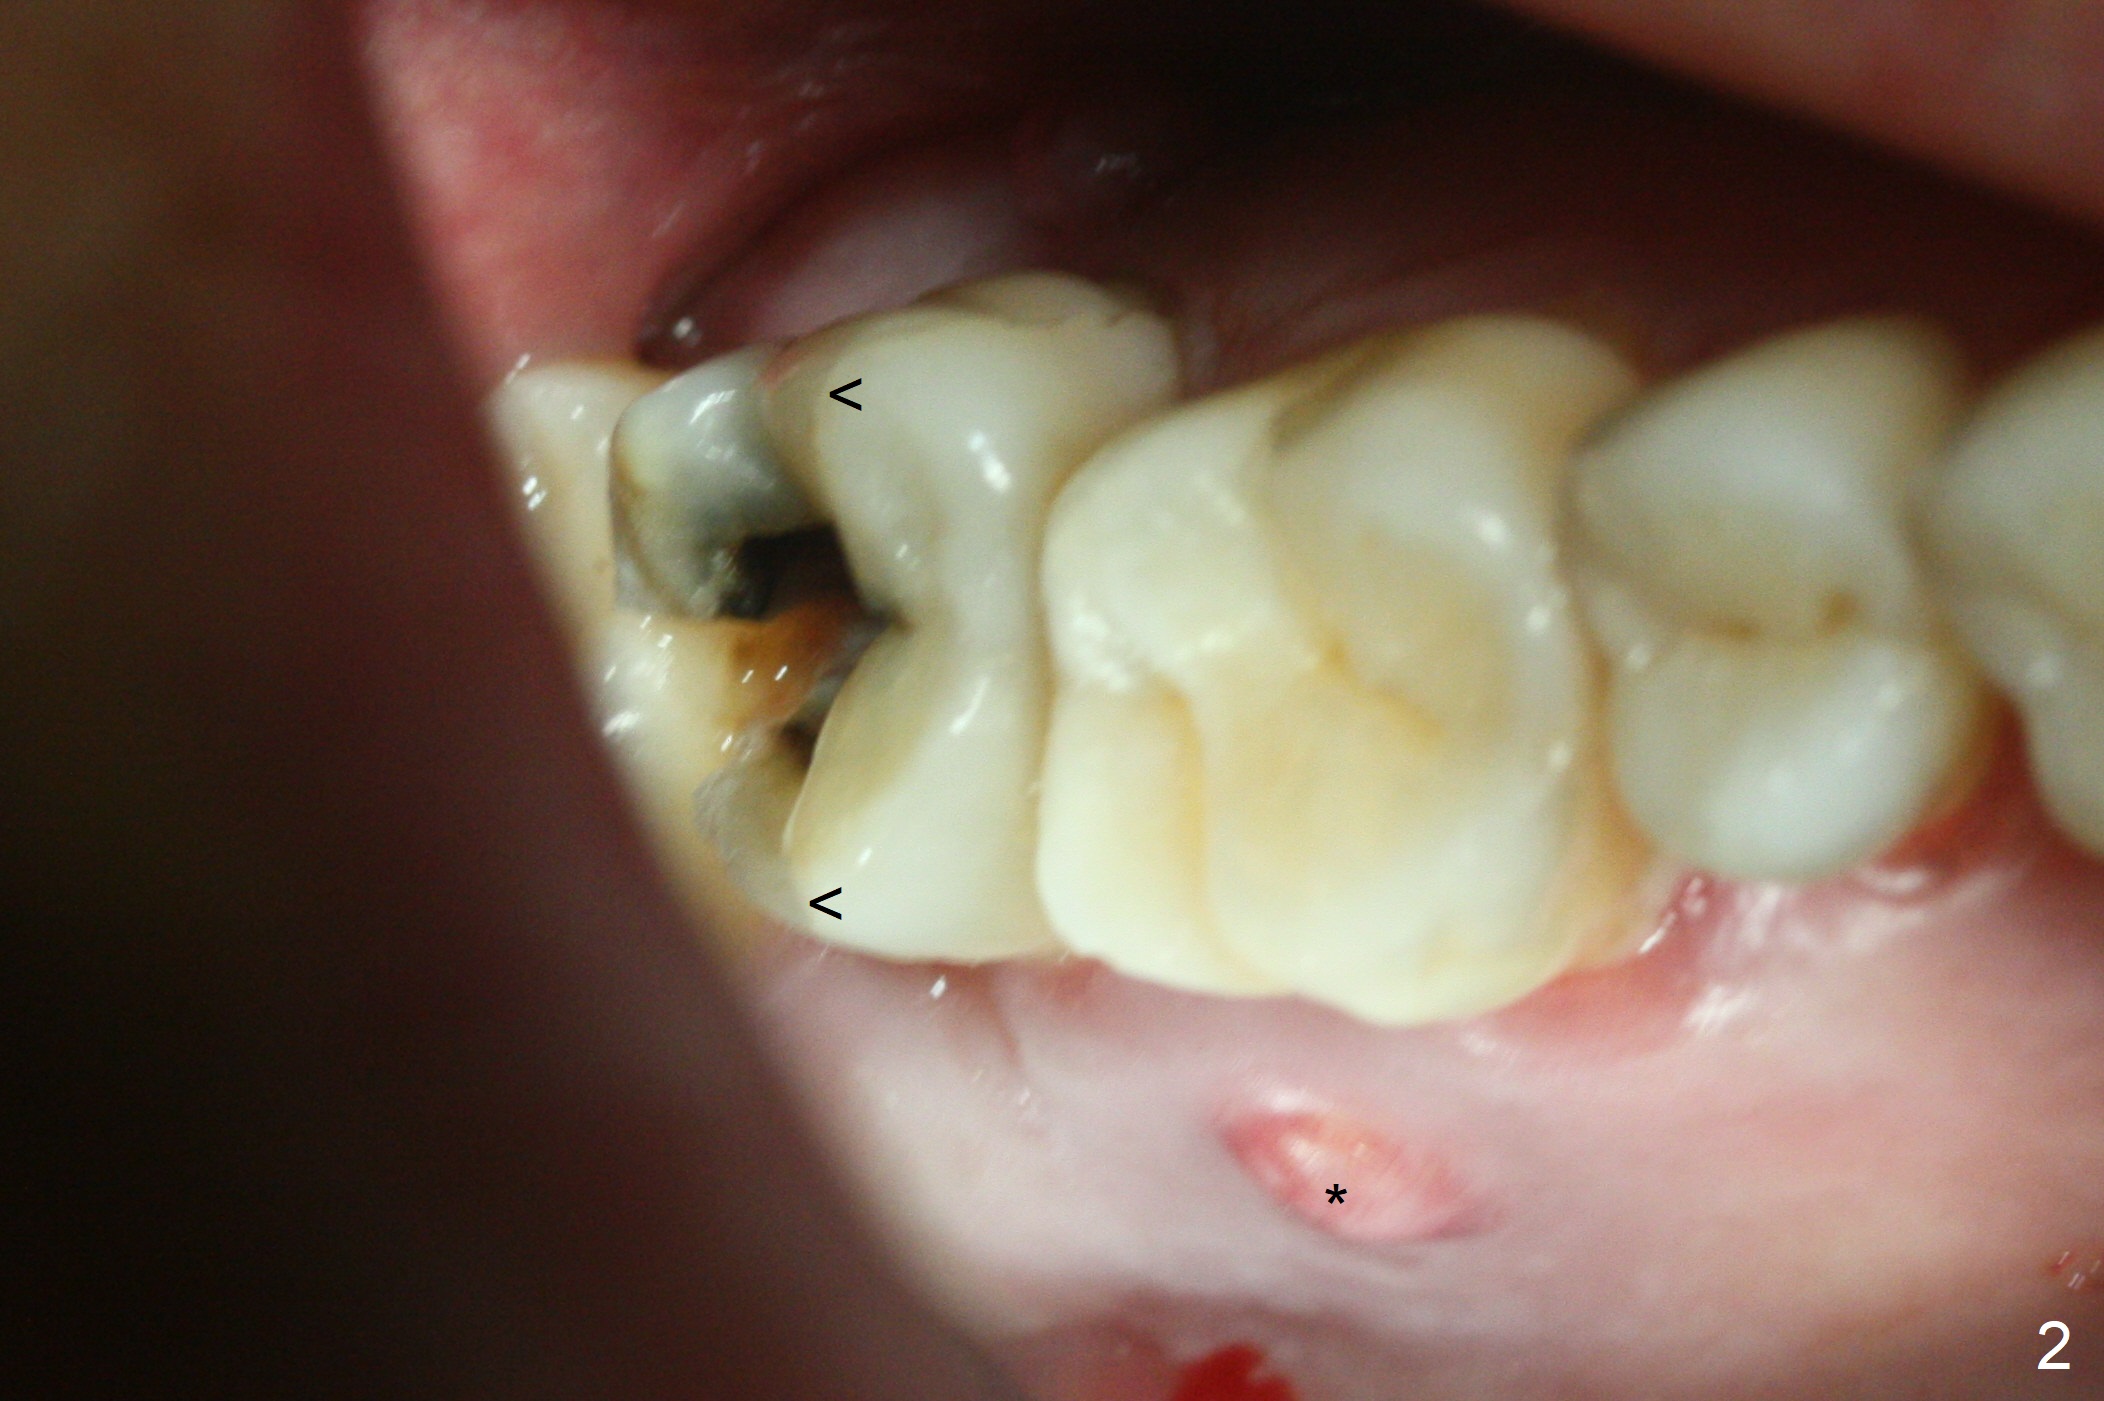

When the 59-year-old man returns for #24 implant placement, the tooth #2 is found to have crack (Fig.1,2 arrowheads), associated with buccal and palatal fistulae (*) and loss of amalgam (Fig.4 *). Abundant granulation tissue is attached to the roots of the affected tooth (Fig.3), indicating severe bone loss. There is a plateau associated with the septum and buccal sockets, which is the site of osteotomy. Magic split and 3 and 3.8 mm Magic Expanders are used to initiate osteotomy. After use of 4.3 mm Magic Drill for about 3 mm, Osteogen plug and allograft are used for sinus lift, followed by insertion of a 4.5x11 mm dummy implant (Fig.5). When a 5.5x9 mm dummy implant is placed with stability, it appears to be seated cervical (Fig.6,7). When a 6x9 mm IBS implant (definitive) is placed with a 6.5x5.5(4) mm abutment, they are seated too deep for provisional (Fig.8). The implant/abutment are removed and replaced by a 6.5x11 mm one in a shallower position; after trimming the same abutment as mentioned above (Fig.9), an immediate provisional is fabricated to keep bone graft in place. Fabrication of Tap with soft tissue markers will reduce the chance of miscalculation and waste of implants. The coronal threads of the implant are covered with bone 6 months postop (Fig.10). One month later when a permanent crown tries in, the implant is found to be loose and tender. A healing abutment is placed. Six months later, the patient returns for crown retry-in. The tooth #1 seems to have shifted mesially (Fig.11 arrow). When the abutment is placed, the implant remains tender and loose. After implant removal with a wrench, there is no granulation tissue or bony defect, including the intact sinus floor (Fig.12 <). Since the tooth #1 has deep periodontal pockets and mobility, the tooth is extracted with abundant granulation tissue. After debridement, Osteogen plug is placed in the socket of #1, while Vanilla graft is placed at the site of #2 (Fig.13 *). Three weeks later, the socket of #2 heals with exposure of Osteogen plug (Fig.14 (B: buccal)).